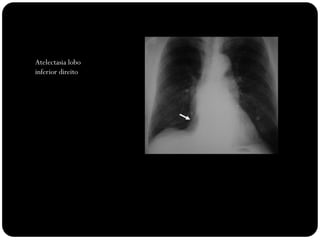

Atelectasia lobo

inferior direito

Observar: